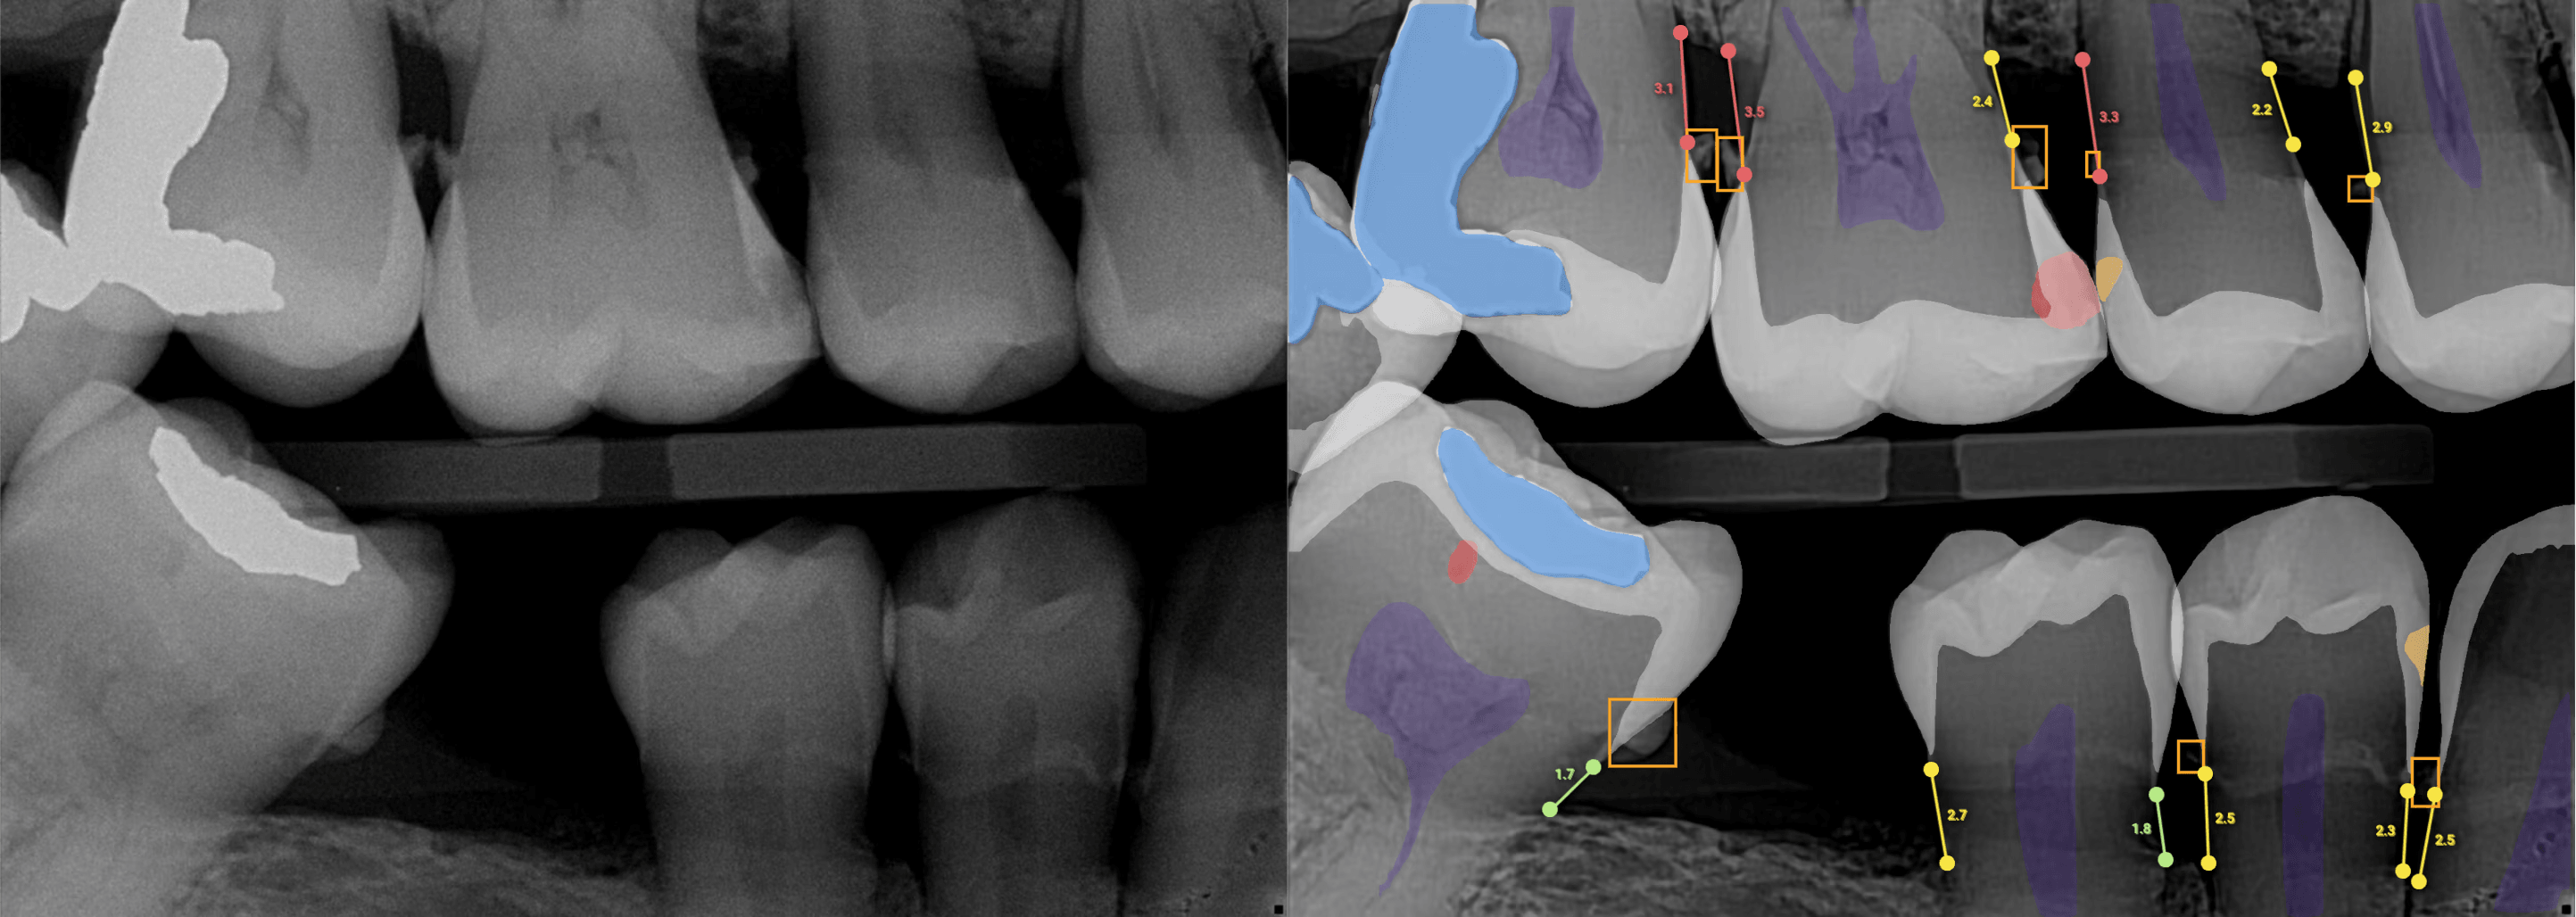

After analysis, AI-generated findings are displayed using clear, color-coded overlays that make complex radiographic information immediately accessible. Each tooth or site can be reviewed individually, with millimeter labels from the cementoenamel junction (CEJ) to the bone crest providing precise measurements. These visual aids transform abstract radiographic data into actionable clinical insights.

The ability to compare baseline and current images side by side proves particularly valuable for tracking disease progression or treatment outcomes over time. Toggle controls allow overlays to be shown or hidden during chairside conversations, giving clinicians flexibility in how they present findings to patients.

For instance, the system provides an annotated case with millimeter labels and a per-tooth chart, which makes it easy to communicate findings to patients and provide objective evidence for insurance claims.